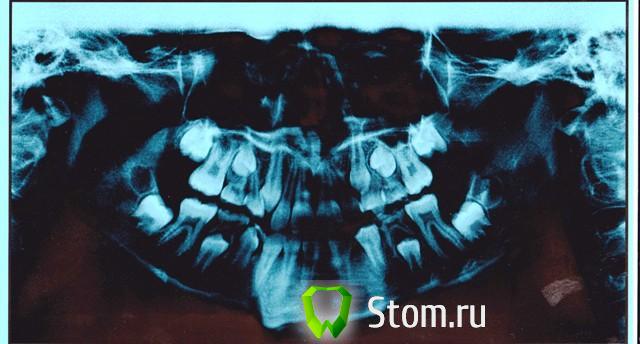

Всем добрый вечер! Прошу совета в непростой ситуации. Дочке 11 лет. Нет места для одного постоянного клыка, лезет вторым рядом, для второго места недостаточно, но есть немного.Молочные клыки удалили в 8 лет. Один врач советует удалить четверки, второй говорит пока повременить, когда вылезут все постоянные зубы, одевать брекеты и действовать по ситуации. Положение еще осложняется тем, что нет внизу двух резцов. Что делать ума не приложу, как не навредить ребенку? Легко сказать удалить четверки. абсолютно здоровые зубы, причем своему собственному ребенку. И нужно ли это? Честно скажу, рука не поднимается и не хватает духу. И как это потом аукнется в более взрослом возрасте никто не знает. Посоветуйте что делать. Заранее спасибо.

Снимки прикрепляю, если не походит качество- перефотографирую.